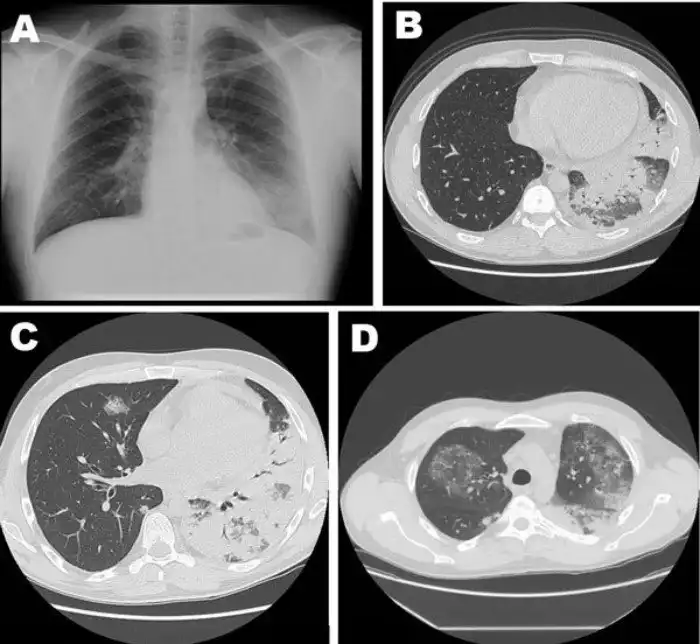

Легкие с прогрессирующей пневмонией, вызванной легионеллой: